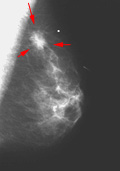

En la mamografía, hay dos signos principales de cáncer: calcificaciones y/o presencia de una masa. Las calcificaciones (depósitos de compuestos de calcio en la mama) aparecen como manchas blancas en una mamografía y ocurren en dos formas, microcalcificaciones y macrocalcificaciones. Las macrocalcificaciones tienden a ser grandes y de aspecto tosco y están asociadas con el envejecimiento. Son comunes en mujeres mayores de 50 años y están presentes en un pequeño porcentaje de mujeres más jóvenes. Las macrocalcificaciones no suelen estar asociadas con el cáncer. Las microcalcificaciones son más pequeñas y se consideran un signo de posible malignidad, incluso sin una masa visible.El radiólogo debe interpretar las características de la masa para determinar la posibilidad de cáncer y ordenará pruebas diagnósticas y posiblemente una biopsia.2

La imagen de la izquierda muestra la mamografía de una mama normal, mientras que la imagen de la derecha muestra una mamografía con una anomalía detectada (indicada por las flechas rojas). Haga clic en las imágnes para visitar su fuente, el Centro de Senos de la Universidad de St. Louis.